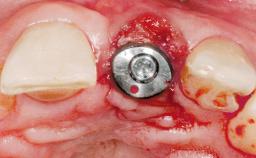

A 42-year-old female patient was referred to our clinic at the School of Dentistry of the University of São Paulo in November 2004, presenting a deficient restoration in the upper left central incisor. The clinical examination revealed no gingival retraction or any signs of gingival inflammation and, therefore, previous periodontal treatment was not considered. The patient presented a high lip line at full smile and a thin tissue biotype. This combination characterized a high-risk situation from an anatomic point of view, which required careful preoperative planning and cautious surgical execution.

Type of Implants One-Piece

Placement Protocol Immediate implant placement

Loading Protocol Immediate

Retention Screw-retained Screw-retained